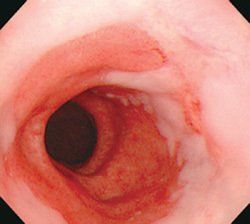

典型的Barrett食管是在胃食管交界上方出現(xiàn)紅色的柱狀上皮區(qū),部分患者可見(jiàn)反流性食管損傷的征象?;顧z可證實(shí)并找到柱狀上皮化生。